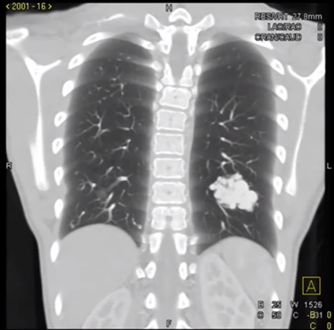

开完检查,我打开影像系统,仔细看了 CT,有五个大小不一的结节,直径在 0.5~2.0cm,其中两个可以看到有动脉并入结节——不过,这和患者的黑便没什么关系。

「肺部 CT 看了一眼,感觉像是多发的动静脉畸形,结合流鼻血和消化道出血,怀疑是遗传性出血性毛细血管扩张症。」主任经典答疑环节开始了,「为了排查可能会危及生命的脑部动静脉畸形,我才让你开了最要紧的头颅磁共振。」

1.png

肺部动静脉畸形   图源:YouTube 截图,非本病例